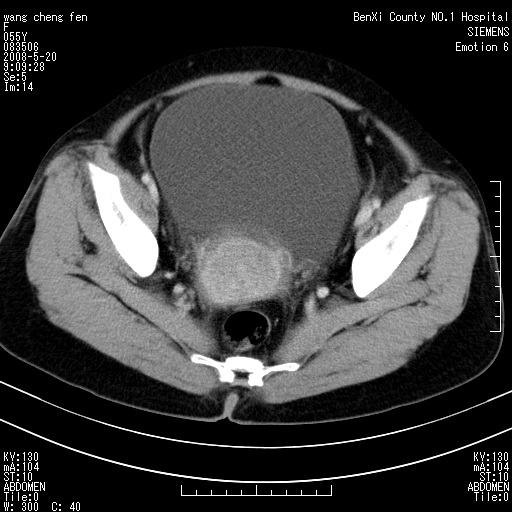

女、绝经后阴道流血3个月

左侧附件区巨大囊实性病灶,边缘光整,病灶囊壁较厚,增强示囊壁及实性部分明显强化,强化呈度与宫体实质大致相同,宫腔积液征像,未见盆腔积液等其他异常,考虑左侧卵巢囊腺癌,不除外囊腺瘤及浆膜下肌瘤坏死

左侧附件区巨大囊实性病灶,边缘光整,病灶囊壁较厚,增强示囊壁及实性部分明显强化,强化呈度与宫体实质大致相同,宫腔积液征像,未见盆腔积液等其他异常。绝经后阴道流血3个月,结合病史左侧卵巢囊腺癌首先考虑,宫腔扩大不除外累及。期待结果。

支持浆膜下子宫肌瘤.之前由于网络原因未看全图片,现在重看,宫颈见一类圆形低密度影,增强轻度强化,低于肌层强化,宫腔扩大,考虑宫颈癌伴宫腔积液可能性大.

1,宫颈部占位,宫颈癌?2,左侧附件区囊实性占位,界较清,实质部分强化明显。考虑浆膜下或阔韧带肌瘤囊变可能大。囊腺类肿瘤不除外。